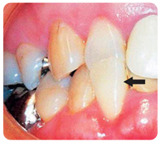

小学校3年生ぐらいから中学生頃までは、患者自身によって取りはずしを行う簡単な矯正装置を使って治療します。いくつかある矯正装置の中でも当院でよく使用するのが、インクラインという矯正装置で、寝る前2時間程度と寝ている間に装着します。この装置は使用しているのが家にいる時だけなので他の人に矯正治療をしていることが知られません。この装置を口の中に装着したところ、また装置を側面から見たところを写真で示します。

写真で見ると治療は大変そうに見えますが、子供達はすぐに慣れて使用できます。

次に実際にこの装置だけ使用して治療した患者さんの例を写真で示します。

このようにこの装置は単純な装置ではありますが、非常に効果があることがお判りいただけると思います。成長期を利用して治療を行うことにより、簡単な装置で肉体的、精神的、費用的にも負担が少なく良好な結果が得られることから、早い時期からの矯正治療をお勧めします。